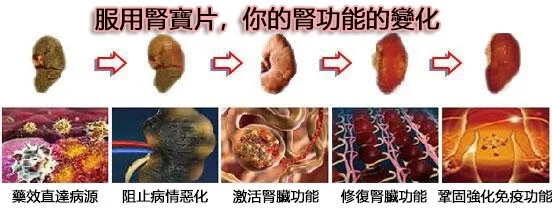

用上就見效,一瓶腎氣足,兩瓶排出體內毒素,三瓶五瓶修復鞏固腎功能

【雲杉腎寶片】能有效的改善修復腎功能,增強體質,解決腎疾病帶來的痛苦。

全面改善腎功能 提高人體糖排毒、代謝通道

【腎寶片】裡面有效成分可直接覆蓋人體腎臟、肝臟、與糖代謝息息相關的組織器官,調節人體生物正負能量,調節陰陽離子,恢復腎臟失衡失序的生理功能,為人體自身糖代謝營造良好的內環境。

腎乃人體的先天之本,腎好百病不生。

【雲杉腎寶片】有效治療:糖腎、尿蛋白、尿酸、高腎、腎虛、肌酐高、腎囊腫、腎衰竭等各種腎疾病。全面改善你的腎臟功能,增強體質!

全面改善腎功能

提高人體糖排毒、代謝通道

【腎寶片】裡面有效成分可直接覆蓋人體腎臟、肝臟、與糖代謝息息相關的組織器官,調節人體生物正負能量,調節陰陽離子,恢復腎臟失衡失序的生理功能,為人體自身糖代謝營造良好的內環境。